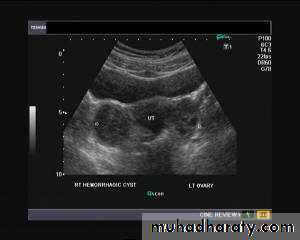

Hemorrhagic cyst of ovary resulting from Ovulation inductionThis young nulliparous female patient undwerwent ultrasonography following ovulation induction. The right ovary shows a typical hemorrhagic cyst formed from the corpus luteum. The first image (top row- left) is a transabdominal ultrasound image showing fine fibrinous strands within the cystic mass in the right ovary. Transvaginal ultrasound and color Doppler images confirm these findings. The uterus shows typical secretory changes in the endometrium suggesting post ovulatory phase.

Hemorrhagic ovarian cysts: